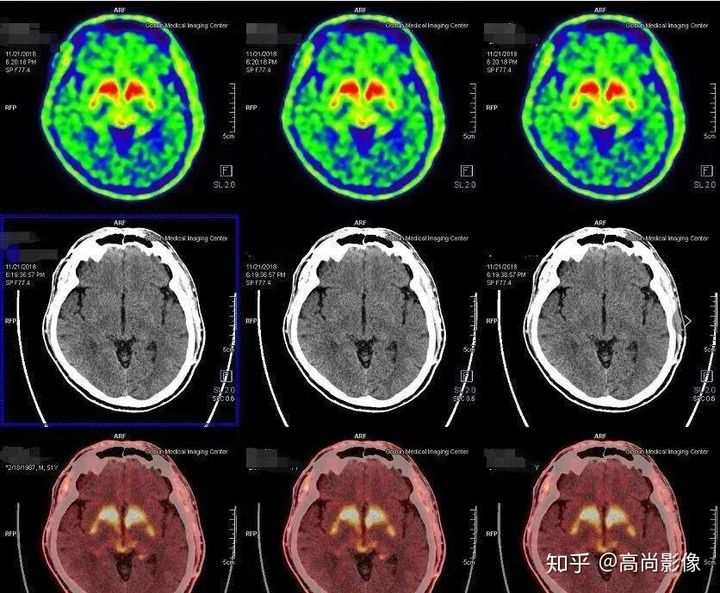

相比之下,童大媽就沒有這么幸運了。除了右邊身子總是抖動,童大媽還有嗅覺障礙、動作緩慢等癥狀。童大媽的PET/CT檢查結(jié)果符合帕金森的表現(xiàn),為臨床診斷提供了重要依據(jù)。

雙側(cè)尾狀核多巴胺轉(zhuǎn)運體分布對稱,左側(cè)殼核后部多巴胺轉(zhuǎn)運體分布較對側(cè)明顯減少,結(jié)合童大媽癥狀,先考慮帕金森。